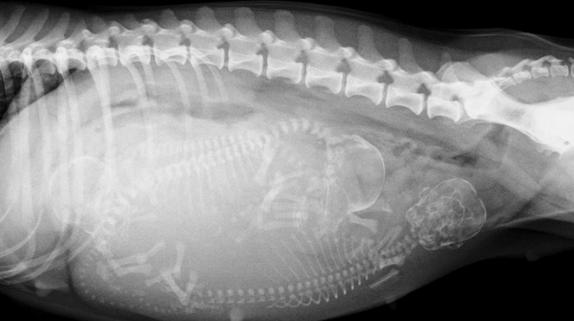

约在怀孕43-45天后拍摄X线片可以明显的看到小猫的骨骼~(请放心这时的X线片是不会对怀孕猫咪及小猫造成伤害的)。而约20天时,通过B超检查探测到的小猫心脏的跳动也是它们在告诉你“我很好~!请不要担心我!”